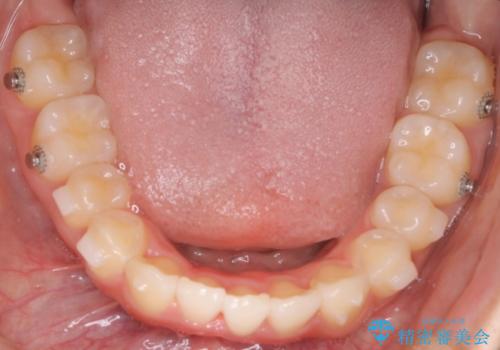

【インビザライン】前歯を下げたい。

- 前歯が出ていることを主訴に来院されました。

下顎前歯が1本欠損していることもあり、前突はある程度残ることを説明し、インビザラインにて治療を行いました。

今回は抜歯矯正ではなく歯列弓の拡大とIPR、遠心移動を行って配列することができました。

下顎前歯が1本少ないため、上下の正中は合いません。